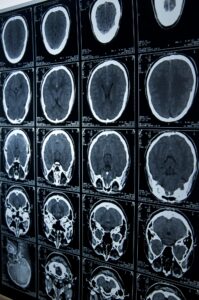

Catastrophic injuries, such as traumatic brain injury (TBI), can have life-altering consequences in Colorado. These severe injuries often result from accidents like car crashes or falls and can profoundly impact a person’s cognitive functions, physical abilities, and overall quality of life. The physical, emotional, and financial burdens on victims and their families can be overwhelming, considering the need for extensive long-term care and rehab in these cases.

Types of Traumatic Brain Injuries that May Occur in Accidents

Common types of traumatic brain injuries following accidents include: